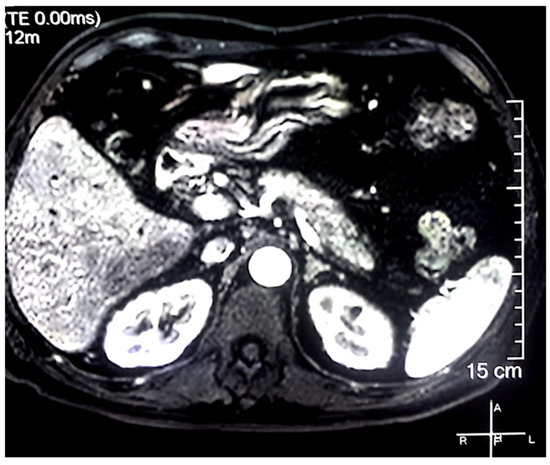

2. Case Report